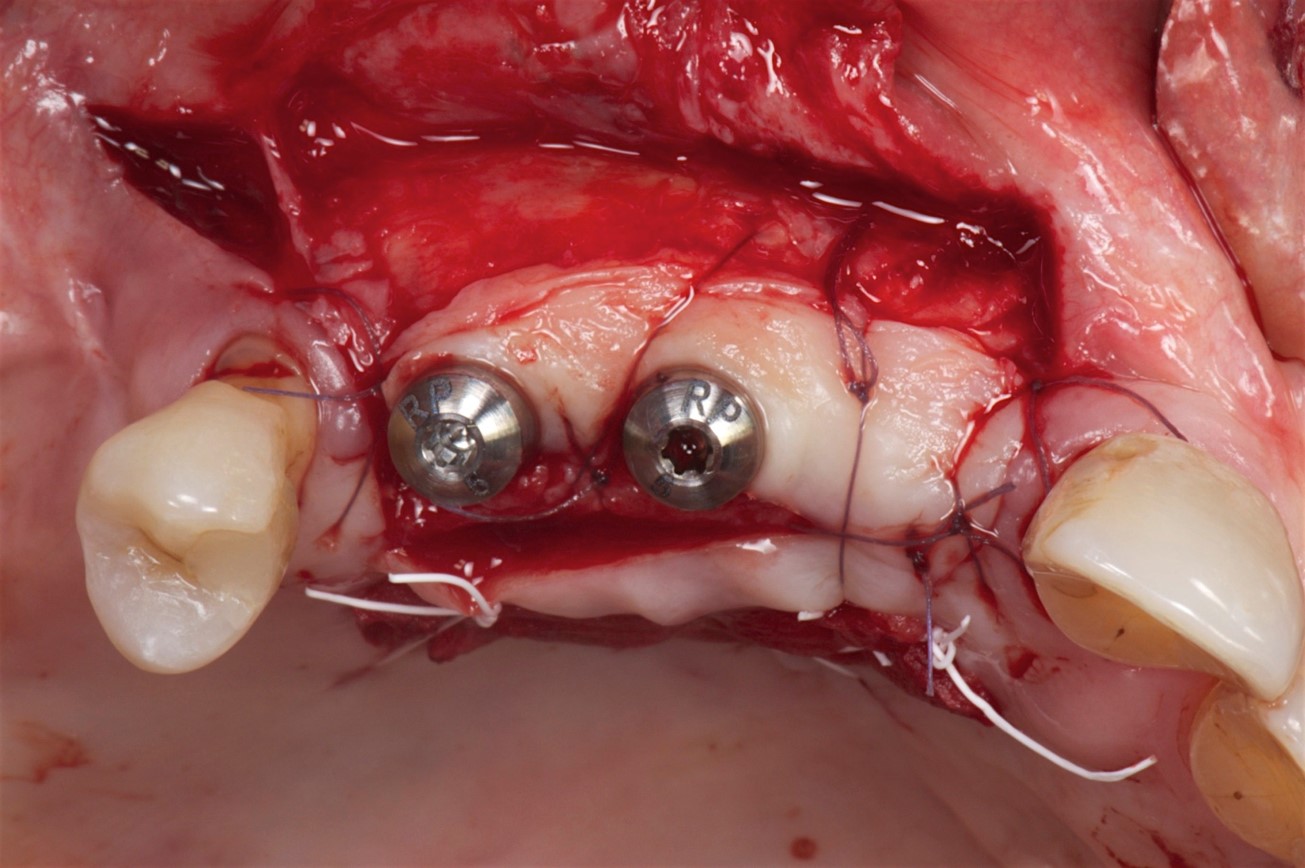

Fig 9. The implants and healing caps were placed.

Figure 9

The implants and healing caps were placed (Figure 9). Implant stability was verified, and a second incision was made to prevent tension on the flap. A second layer of deproteinized bovine bone was placed to augment the site volume as much as possible, after which a collagen matrix was placed to augment the soft-tissue thickness. Horizontal mattress sutures were placed without tension, followed by very thin stitches.